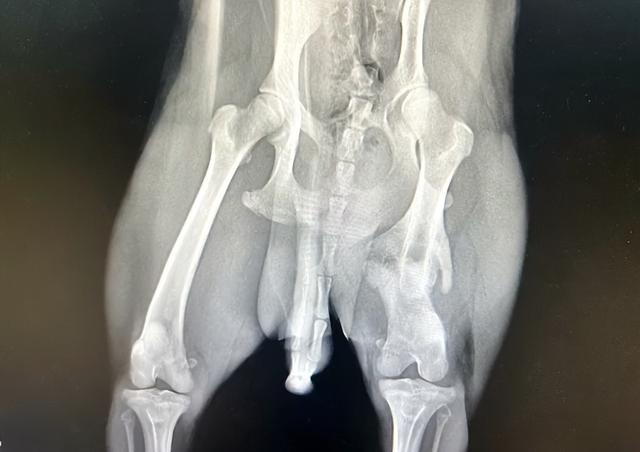

狗狗的拍片结果显示,它曾经多次受伤

检查完狗狗的情况之后,小哥就和同伴一起带着这只受伤的柴犬告别了好心的阿姨,然后把这只柴犬带到了宠物医院里。而在前往宠物医院的路上,这只柴犬也是特别的乖巧,全程一直乖乖地趴在小哥身边,既没有吠叫,也没有任何的挣扎。于是,在狗狗的配合下,小哥和他的同伴顺利地来到了宠物医院。之后,经过宠物医生的一番检查,这只柴犬的两条腿都有骨折,并且,通过骨痂推断,狗狗受伤的时间已经有20多天了。

同时,在宠物医生的检查过程中,他们还发现,狗狗的前腿还有新伤。而这些,无一不在说明着,可能它在曾经的主人那里过得并不那么好,甚至可能还备受伤害。可让小哥意外的是,哪怕狗狗受到如此多的伤害,它依然还是选择用温暖的笑容回报人类,给人们最大的信赖的同时,也用笑容温暖着每个靠近它的人,只是,也不知它的笑容是否让它曾经的主人有所改变……